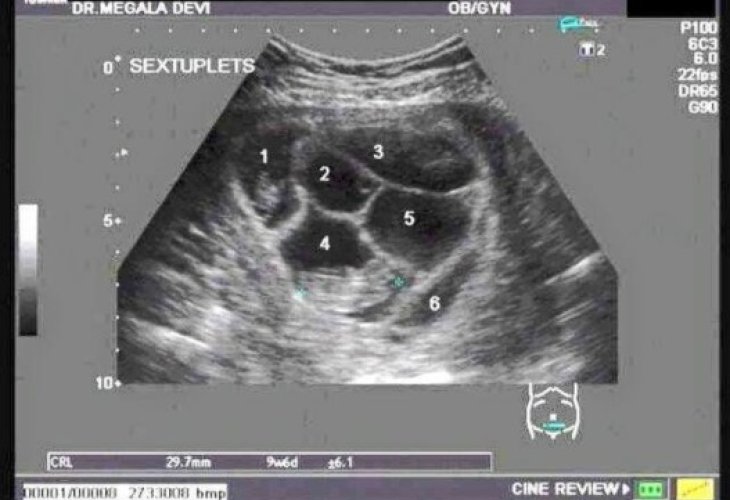

But two months later, during a routine ultrasound, the doctor surprised them with a rare sight in the womb: "I hope you are calm, relaxed, and able to receive peacefully the news I’m about to give you: Congratulations, you have five embryos," the doctor announced.

"Before I could even react, the doctor suddenly said, 'Wait, wait, I see something else. Sorry, not five. Look, I see another embryo, you have six children,'" recounts a stunned Lauren, who was now faced with the toughest decision of her life: whether to bring all six children into the world or not.